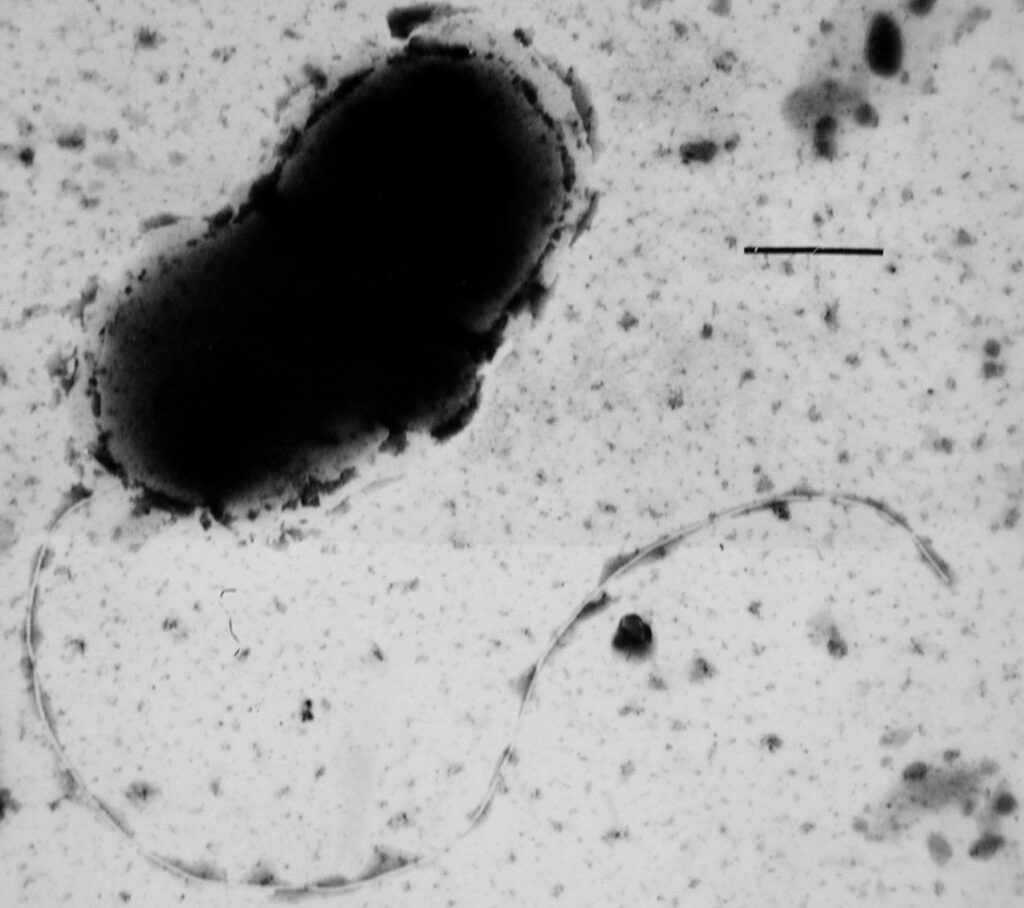

Il y a quelques bactéries susceptibles de se développer dans votre chauffe-eau, mais la plus courante est la légionelle.

La légionelle est la bactérie qui cause la maladie du légionnaire. Vous pouvez contracter la maladie des légionnaires en inhalant des microgouttelettes d’eau contaminée par la légionelle. La maladie du légionnaire est un type grave de pneumonie. Il provoque une inflammation des poumons, des courbatures et des douleurs musculaires, une forte fièvre et parfois des toux sanglantes. Cela vous causera également des douleurs thoraciques, un essoufflement et une confusion mentale à mesure que cela s’aggrave.

Bien que la maladie du légionnaire puisse être traitée et qu’elle ne soit pas transmissible, c’est loin d’être quelque chose que vous souhaitez contracter. Elle peut même être mortelle pour les personnes âgées et dont le système immunitaire est affaibli. Compte tenu de cela, il est important de s’assurer que les bactéries Legionella ne peuvent pas se développer dans votre chauffe-eau.